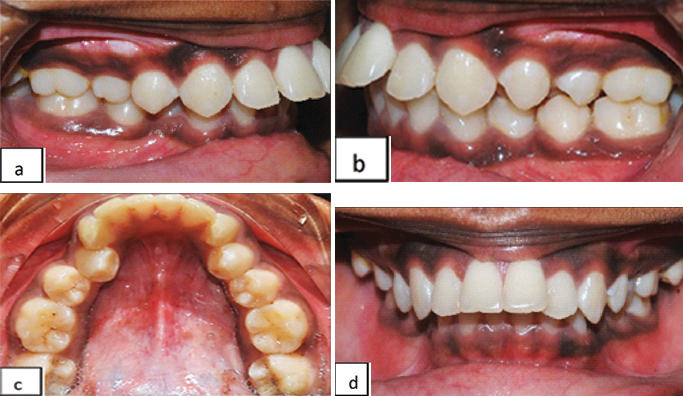

A 19-year-old female patient reported to the department with a mutilated malocclusion [Table/Fig-6a,b] and deep bite [Table/Fig-6c] on a skeletal Class II jaw base. Intraoral examination revealed missing lower first molars bilaterally which were extracted earlier due to caries and also mild lower anterior crowding [Table/Fig-6d]. In this case, we had planned to upright the lingually tipped second molars bilaterally and to mesialize the second molars to the position of the first molars as the third molars were present and this would avoid the prosthetic replacement of the missing molars.

Pre-treatment shows: a,b) mutilated malocclusion; c) deep bite; d) lingually tipped mandibular second molars bilaterally and missing first molars.